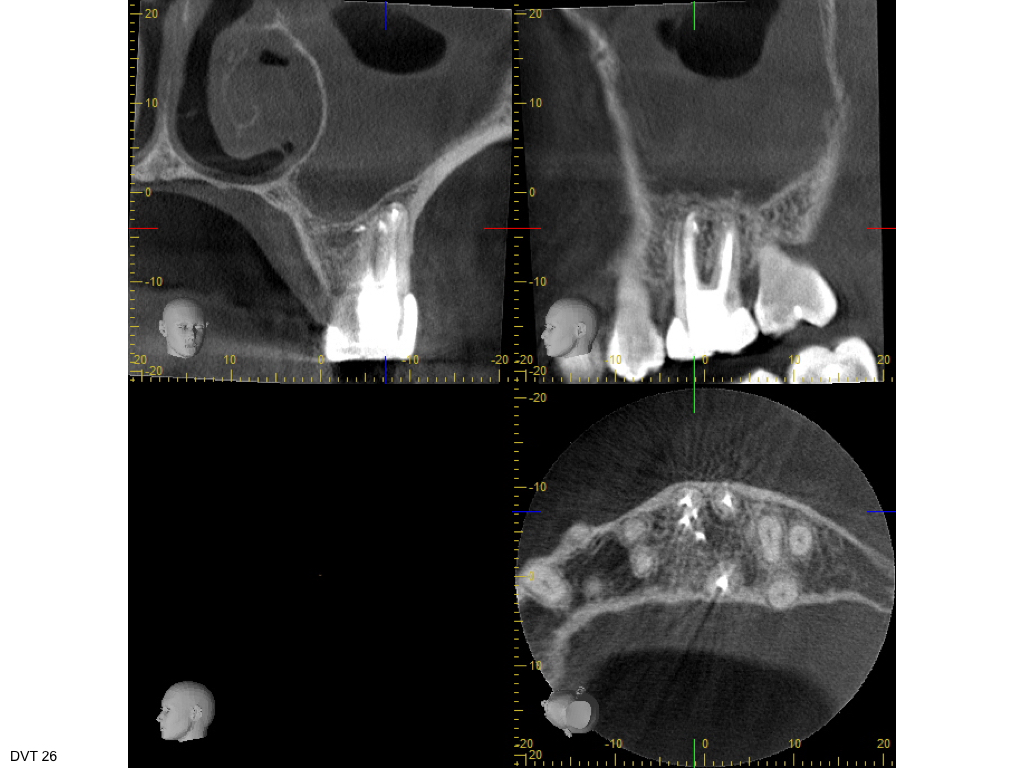

ws-29092016-009

Heilung oder was?